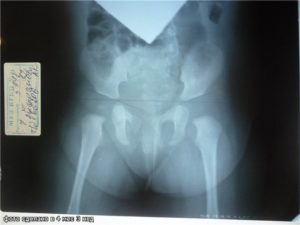

Если тазобедренный сустав имеет связанную с развитием ядра патологию, ее обнаружит УЗИ. Для ее выявления применяют и методы сонографического исследования. Часто может потребоваться и рентгенологическое исследование таза. Рентгеновский снимок для этого выполняется в прямой проекции.

Он дает возможность врачам получать максимально точную информацию о наличии или отсутствии патологии.

Патология ядра выявляется при помощи ультразвукового и сонографического исследования. Дополнительно проводится рентген поврежденных суставов таза. Для рентгеновского снимка выбирается прямая проекция, благодаря чему врачи могут получить более точную и подробную информацию о состоянии опорно-двигательного аппарата ребенка.